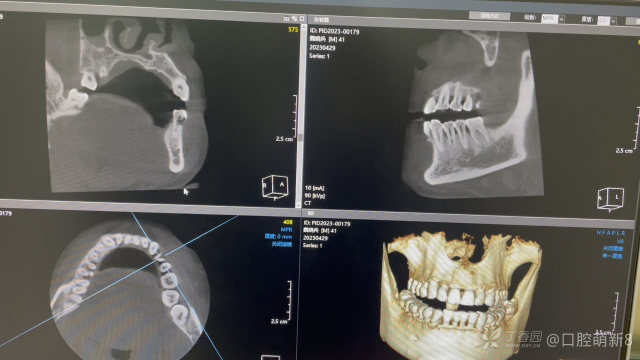

求助求助,帮忙看一下这个是纵裂吗(>﹏<)

口腔萌新8全科医师

左下4,主诉要求补楔缺。检查可探及根管口,开髓后有探痛,放了一次失活。一周后复诊,拔髓,有血渗出,置cp棉球开放。3天后复诊,渗出不多,拔髓有少量牙髓,楔缺补了,20号的h挫根管口下去一两个毫米就显示超,根管已吹干。这个是怎么回事呀,求指教。